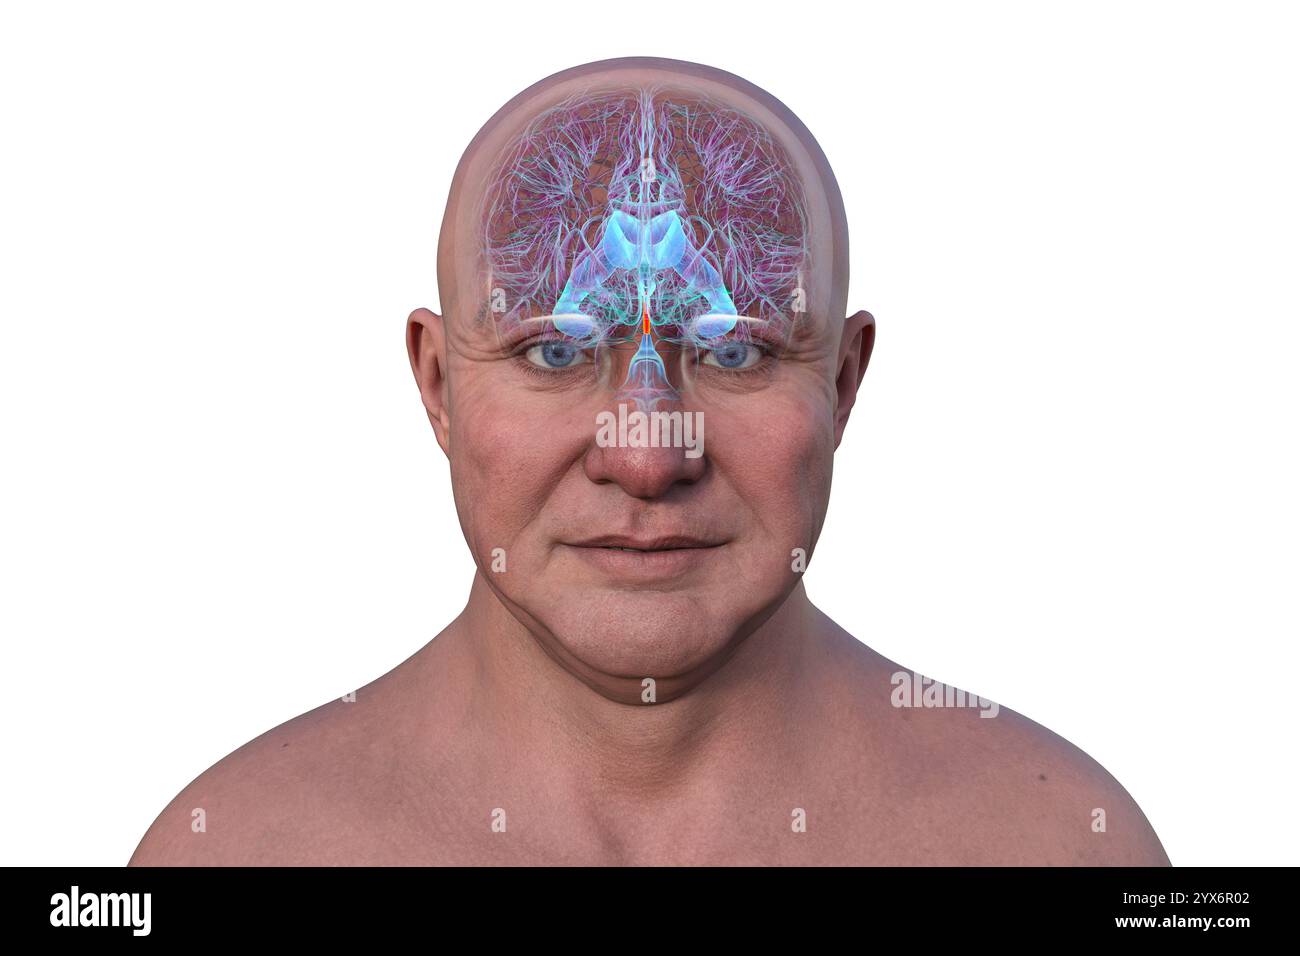

RF3C7H8A6–Abbildung des Gehirns mit hervorgehobenem Aquädukt (rot) und ventrikulärem System (blau), Darstellung des Liquorflusses.

RF3C7H8A3–Abbildung des Gehirns mit hervorgehobenem Aquädukt (rot) und ventrikulärem System (blau), Darstellung des Liquorflusses.

RF2YX6R0N–Computerdarstellung des menschlichen Gehirns mit orangefarbenem Aquädukt und grünem Ventrikelsystem, die den Liquorfluss (CSF) zeigen.

RF2YX6R0K–Computerdarstellung des menschlichen Gehirns mit orangefarbenem Aquädukt und grünem Ventrikelsystem, die den Liquorfluss (CSF) zeigen.

RF2YX6R02–Computerdarstellung des menschlichen Gehirns mit orangefarbenem Aquädukt und grünem Ventrikelsystem, die den Liquorfluss (CSF) zeigen.

RF2YX6R05–Computerdarstellung des menschlichen Gehirns mit orangefarbenem Aquädukt und grünem Ventrikelsystem, die den Liquorfluss (CSF) zeigen.

RF2YX6R0G–Computerdarstellung des menschlichen Gehirns mit orangefarbenem Aquädukt und grünem Ventrikelsystem, die den Liquorfluss (CSF) zeigen.

RF2YYB746–Computerdarstellung des menschlichen Gehirns mit orangefarbenem Aquädukt und grünem Ventrikelsystem mit Liquorfluss.

RF2YYB74E–Computerdarstellung des menschlichen Gehirns mit orangefarbenem Aquädukt und grünem Ventrikelsystem mit Liquorfluss.

RF2YYB751–Computerdarstellung des cerebralen Aquädukts (orange), eines schmalen Kanals im Mittelhirn, der den dritten und vierten Ventrikel verbindet und den Liquorfluss erleichtert.

RF2YYB74X–Computerdarstellung des cerebralen Aquädukts (orange), eines schmalen Kanals im Mittelhirn, der den dritten und vierten Ventrikel verbindet und den Liquorfluss erleichtert.

RF2YYB75A–Computerdarstellung des cerebralen Aquädukts (orange), eines schmalen Kanals im Mittelhirn, der den dritten und vierten Ventrikel verbindet und den Liquorfluss erleichtert.

RF2YYB741–Computerdarstellung des menschlichen Gehirns mit orangefarbenem Aquädukt und grünem Ventrikelsystem mit Liquorfluss.

RF2YYB742–Computerdarstellung des menschlichen Gehirns mit orangefarbenem Aquädukt und grünem Ventrikelsystem mit Liquorfluss.

RF2YYB754–Computerdarstellung des cerebralen Aquädukts (orange), eines schmalen Kanals im Mittelhirn, der den dritten und vierten Ventrikel verbindet und den Liquorfluss erleichtert.

RF2YYB75B–Computerdarstellung des cerebralen Aquädukts (orange), eines schmalen Kanals im Mittelhirn, der den dritten und vierten Ventrikel verbindet und den Liquorfluss erleichtert.

RF2YYB759–Computerdarstellung des cerebralen Aquädukts (orange), eines schmalen Kanals im Mittelhirn, der den dritten und vierten Ventrikel verbindet und den Liquorfluss erleichtert.

RF2YYB755–Computerdarstellung des cerebralen Aquädukts (orange), eines schmalen Kanals im Mittelhirn, der den dritten und vierten Ventrikel verbindet und den Liquorfluss erleichtert. Rückansicht.

RF2YYB752–Computerdarstellung des cerebralen Aquädukts (orange), eines schmalen Kanals im Mittelhirn, der den dritten und vierten Ventrikel verbindet und den Liquorfluss erleichtert. Rückansicht.

RF2YYB75E–Computerdarstellung des cerebralen Aquädukts (orange), eines schmalen Kanals im Mittelhirn, der den dritten und vierten Ventrikel verbindet und den Liquorfluss erleichtert. Ansicht von unten.